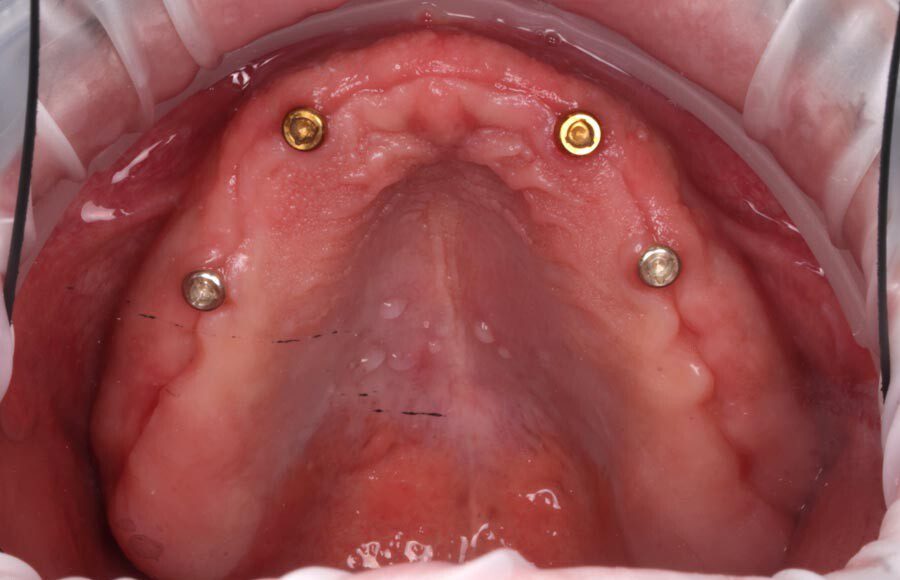

Smile GalleryImplant RestorationsImplant Dentures Post-op smiling 1 of 32 Pre-op close up smiling Pre-op lips retracted smiling Pre-op panoramic x-ray Implants in upper jaw (occlusal view) Implants in lower jaw (occlusal view) Panoramic x-ray of implants First set of try-ins – upper denture First set of try-ins – lower fixed provisional Delivered try-ins (lips retracted) Close adaptation to gums and appropriate emergence profile of lower fixed provisional Gum tissues have been molded by a convex provisional Delivered try-ins Second set of try-ins (lips retracted) Close adaptation to gums and appropriate emergence profile of second set of lower fixed provisional Delivered second try-ins Definitive restorations on casts (frontal view) Definitive restorations on cast (right side) Definitive restorations on cast (left side) Definitive upper overdenture (occlusal view) Definitive lower fixed titanium-acrylic hybrid restoration (occlusal view) Definitive lower fixed titanium-acrylic hybrid restoration (frontal view) Definitive lower fixed titanium-acrylic hybrid restoration (tissue side view) Healthy molded gum tissues on lower prior to delivery of lower fixed hybrid restoration Healthy gum tissues on upper prior to delivery of upper overdenture Definitive restorations (frontal, lips retracted) Definitive lower restoration (frontal) Definitive restorations (right side) Definitive restorations (left side) Definitive lower restoration (occlusal view) Definitive upper restoration (occlusal view) Post-op panoramic x-ray Post-op smiling